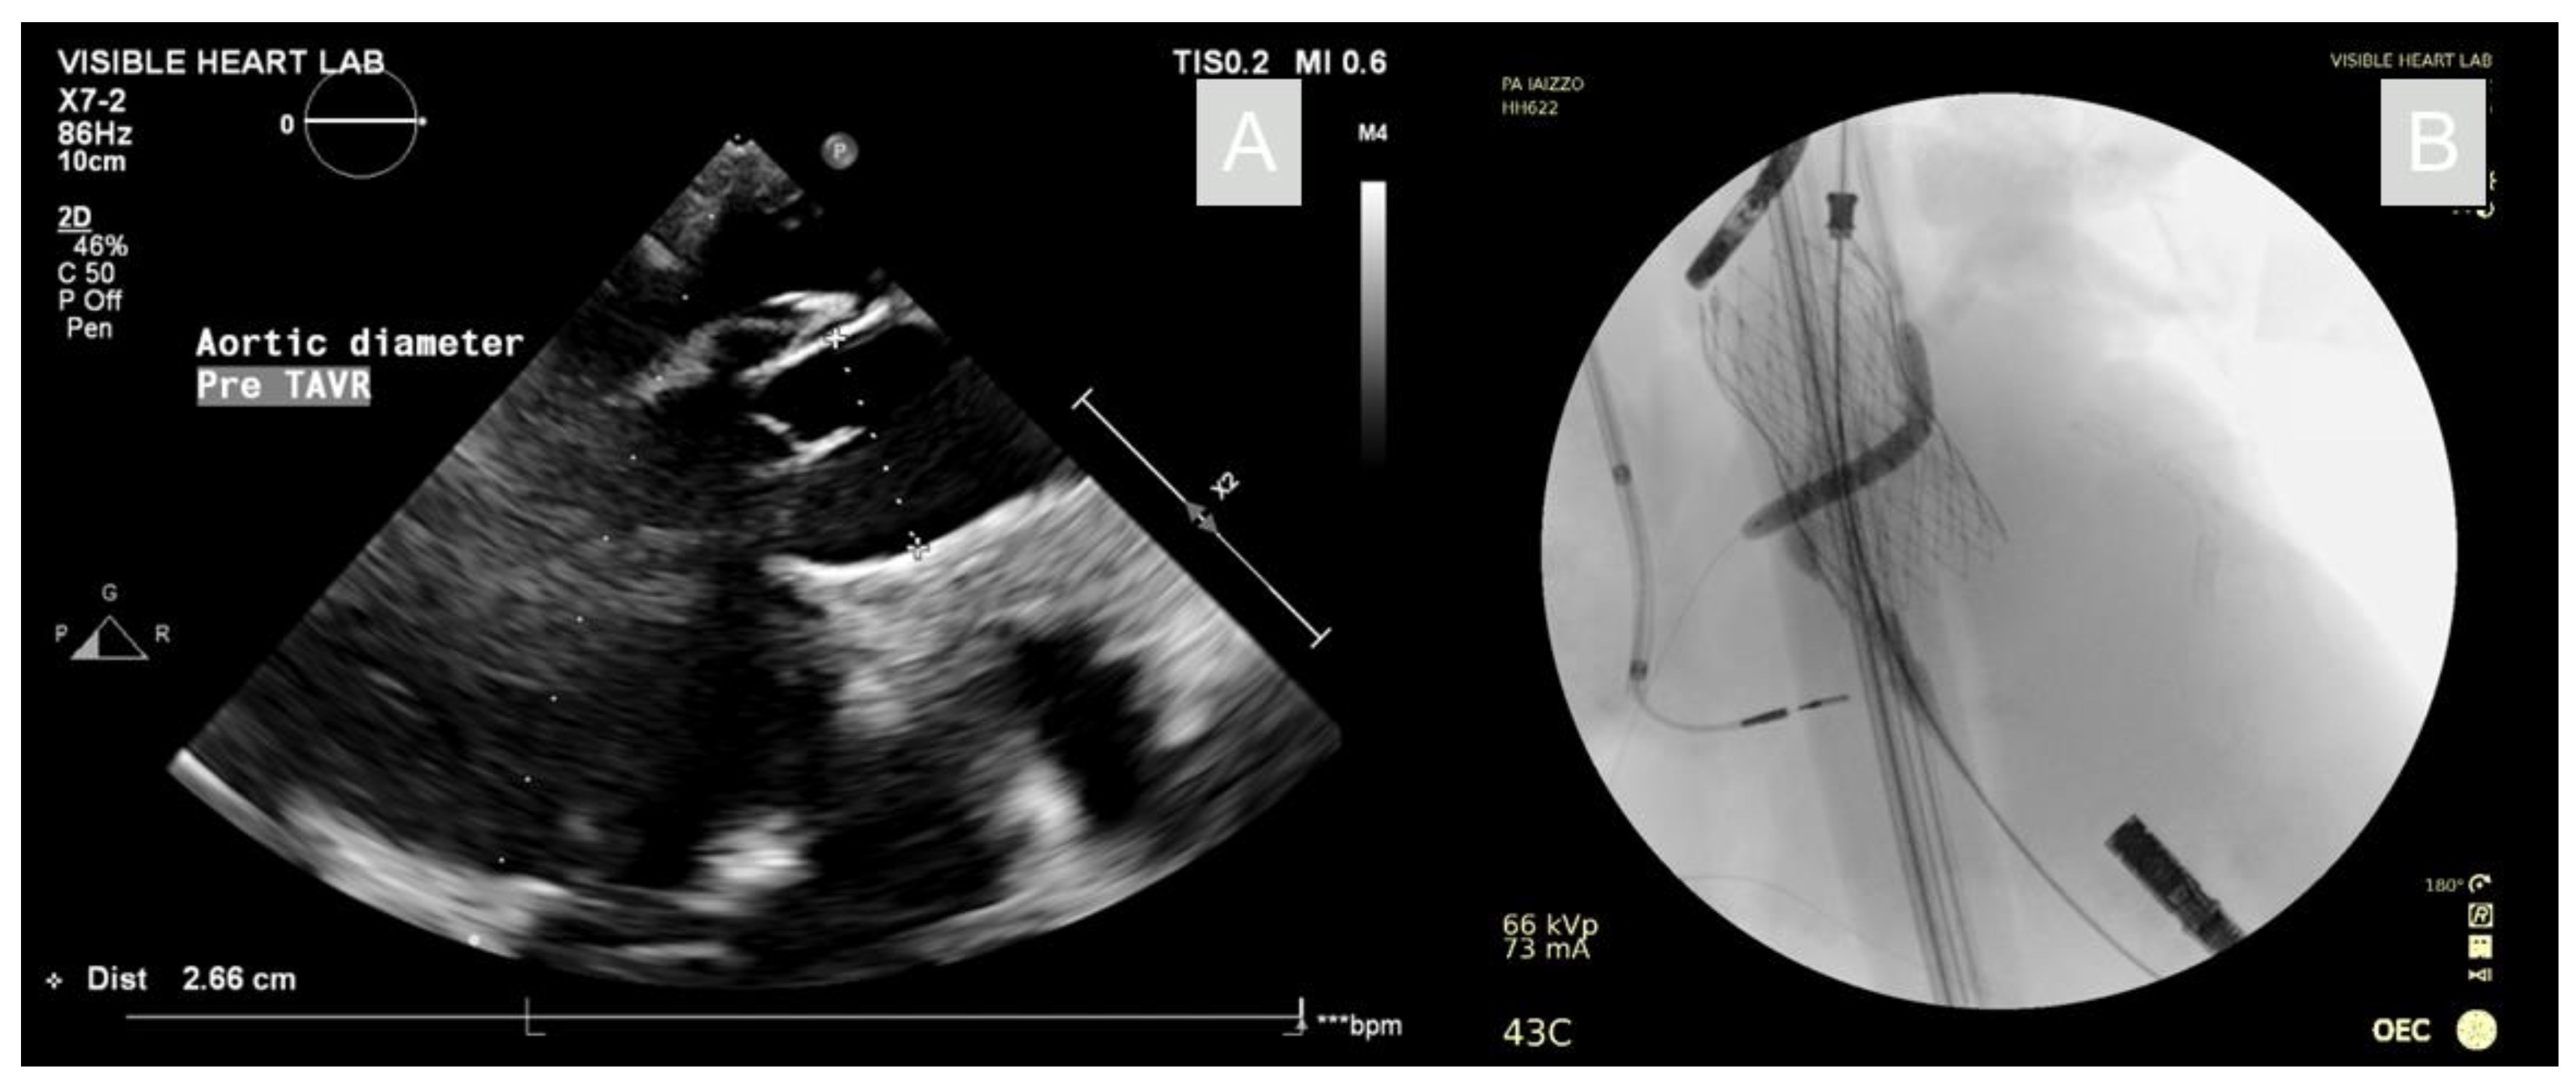

Following the reanimation, it was shown that the anatomic position of the right coronary ostium lay very deep in the coronary cusp, proximal to the annulus. Therefore, if a TAVR procedure alone was conducted in this specimen, the right coronary vessel would likely have a high risk for occlusion. With this in mind, it was determined that, while the aortic valve did not pose indications for a TAVR procedure, we were presented with a unique opportunity to visualize a simultaneous chimney-stenting procedure in functional human anatomies. The aortic annulus was assessed to have a ~26 mm diameter when imaged apically using echocardiography, as seen in Figure 2. Hence, a corresponding 26 mm Evolut™ Pro+ valve was selected and loaded into an 18Fr EnVeo™ delivery system and advanced over a guidewire through the aorta and across the aortic valve. A pigtail catheter was positioned in the non-coronary cusp of the aortic valve prior to the valve deployment. Additionally, a guide wire was passed through the right coronary ostium via a 6F coronary guide catheter (Medtronic, MN, USA). An optical coherence tomography (OCT) scan was performed by advancing a Dragonfly Optis™ catheter (Abbott, IL, USA) over the guidewire and into the coronary artery. A pullback was performed such that an intravascular cross-sectional image was taken every 0.1 mm over 54 mm of a vessel. From the OCT images, the coronary diameter was determined and a 4 mm diameter, 22 mm length Onyx stent (Medtronic, MN, USA) was selected. The stent was advanced over the guidewire, then positioned so it would extend out of the coronary vessel and into the aorta.

Figure 2. Echocardiography with aortic diameter measurement for prosthesis sizing (A). Fluoroscopy of the deployed TAVR and chimney stent with deployment balloon inflated (B).